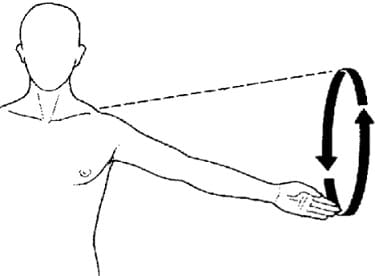

CIRCUNDUCCIÓN